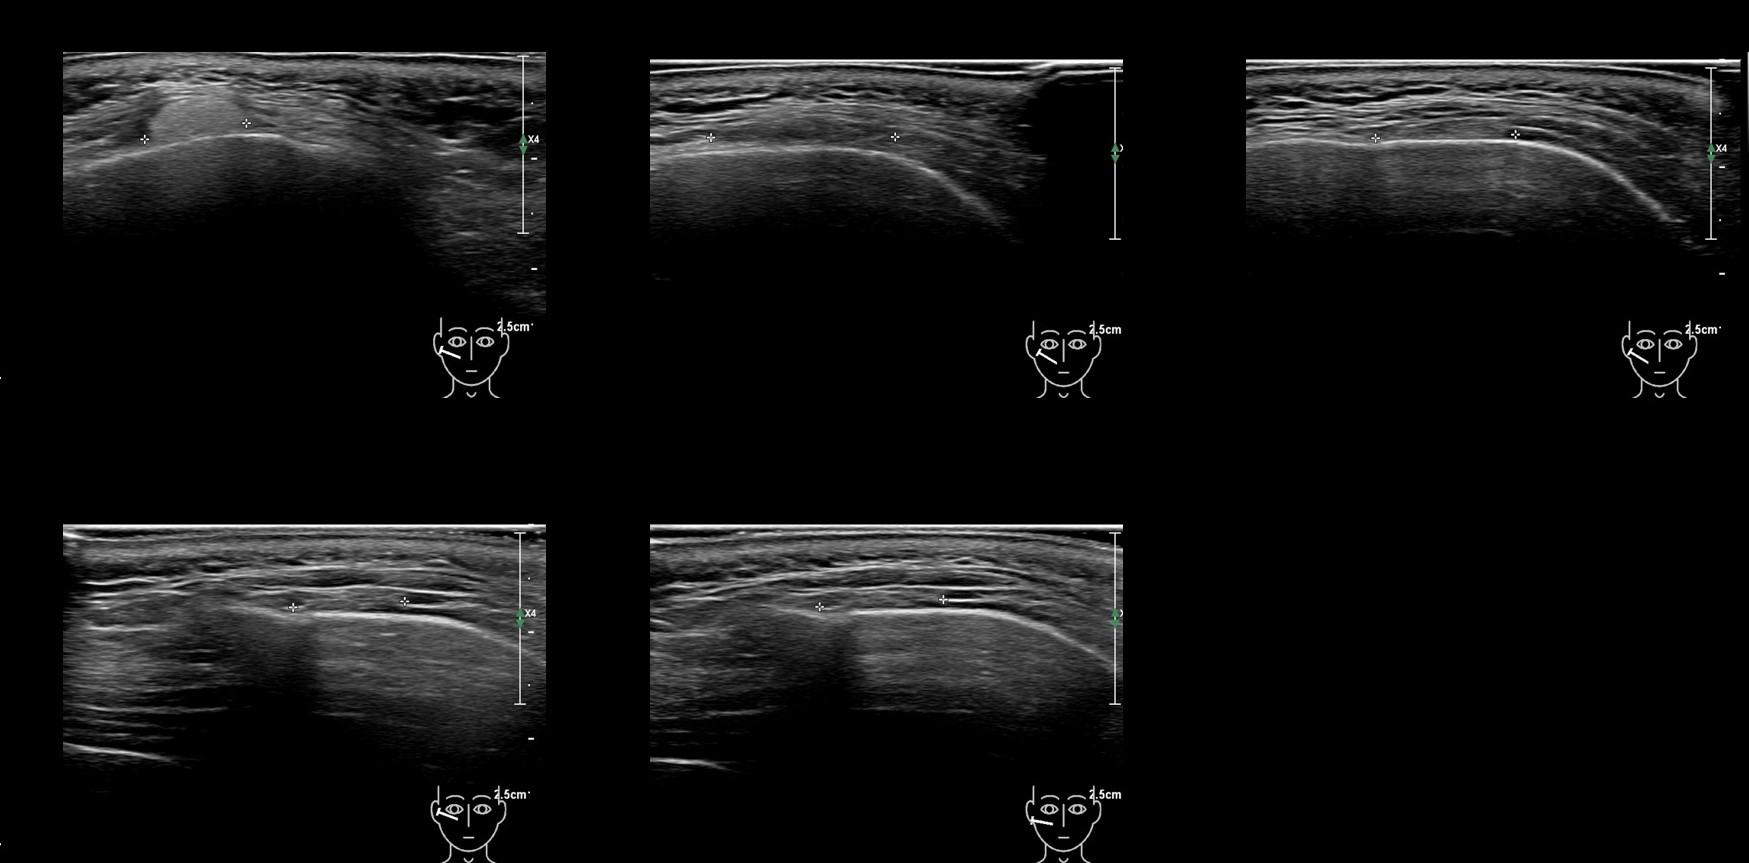

Draw in the image on the right where the fillers are located. To check if your answer is correct, please click on the secondary image.

Draw in the second image below where the fillers are located. To check if your answer is correct, swipe the first image to the right.